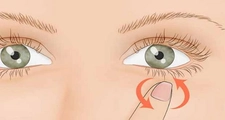

Damar seğirmesi, istem dışı kas kasılmalarıyla karakterize edilen ve genelde zararsız olarak kabul edilen bir durumdur. Belirtileri arasında kas rahatsızlığı, yorgunluk ve uyku bozuklukları yer alır. Tedavi yöntemleri, altta yatan nedenlere bağlı olarak değişiklik gösterir.

Damar seğirmesi, tıptaki adıyla "miyoklonus" olarak bilinen bir durumdur ve genellikle istem dışı kas kasılmaları ile karakterizedir. Bu yazıda, damar seğirmesinin belirtileri, olası nedenleri ve tedavi yöntemleri üzerinde durulacaktır. Damar Seğirmesinin Belirtileri Damar seğirmesi belirtileri, kişiden kişiye değişiklik gösterebilir. Ancak genel olarak aşağıdaki belirtiler gözlemlenebilir:

Damar Seğirmesi Tedavisi Damar seğirmesinin tedavisi, altta yatan nedenlere bağlı olarak değişiklik göstermektedir. Tedavi yöntemleri arasında:

Ekstra Bilgiler Damar seğirmesi genellikle ciddi bir sağlık sorunu olarak değerlendirilmez, fakat sürekli hale gelirse veya diğer belirtilerle birlikte görülürse doktora başvurulması önerilir. Ayrıca, seğirmelerin psikolojik etmenlerden kaynaklandığı düşünülüyorsa, bir psikolog veya psikiyatristle görüşmek faydalı olabilir. Sonuç olarak, damar seğirmesi, çoğu zaman geçici ve zararsız bir durumdur; ancak, belirtilerin sürekli hale gelmesi durumunda profesyonel bir yardım alınması önemlidir. |